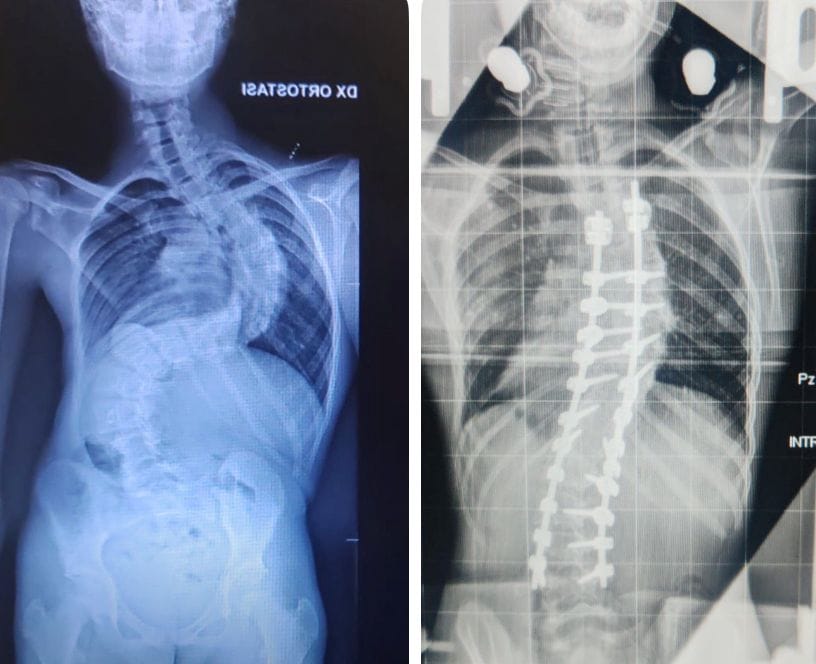

Francesco, spiega il dottor Piazzolla, «era affetto da una forma di scoliosi aggressiva, con un peggioramento impressionante: oltre 30 gradi in appena tre mesi. Una progressione rapidissima – sottolinea – che ha imposto una preparazione preoperatoria complessa e meticolosa».

Per più di un mese il ragazzo ha vissuto stabilmente in ospedale, «sottoposto a trazione continua con un sistema speciale, l’halo, un dispositivo che consente di preparare progressivamente la colonna vertebrale a un intervento tanto delicato grazie al quale siamo riusciti a ridurre la scoliosi a 45 gradi», evidenzia Piazzolla.